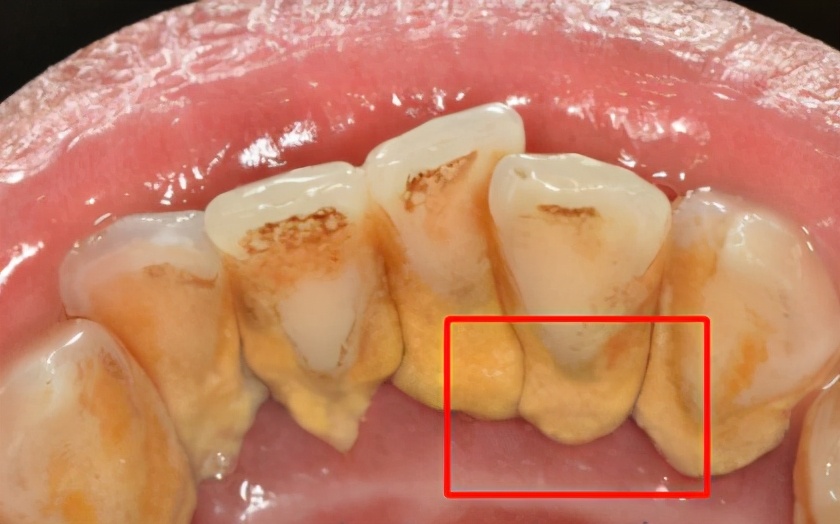

1、牙结石

如果口腔清洁不到位,也没有定期洗牙的话,会积聚大量的牙结石!这些牙结石通常会“扎根”在两颗牙之间的间隙,越积越多则会导致这个缝隙越来越大。

随之而来的是,牙结石发展成牙周炎并且导致牙龈萎缩,使牙根部暴露出来,牙间隙出现牙周炎!在牙结石清除掉后,黑三角就会出现。